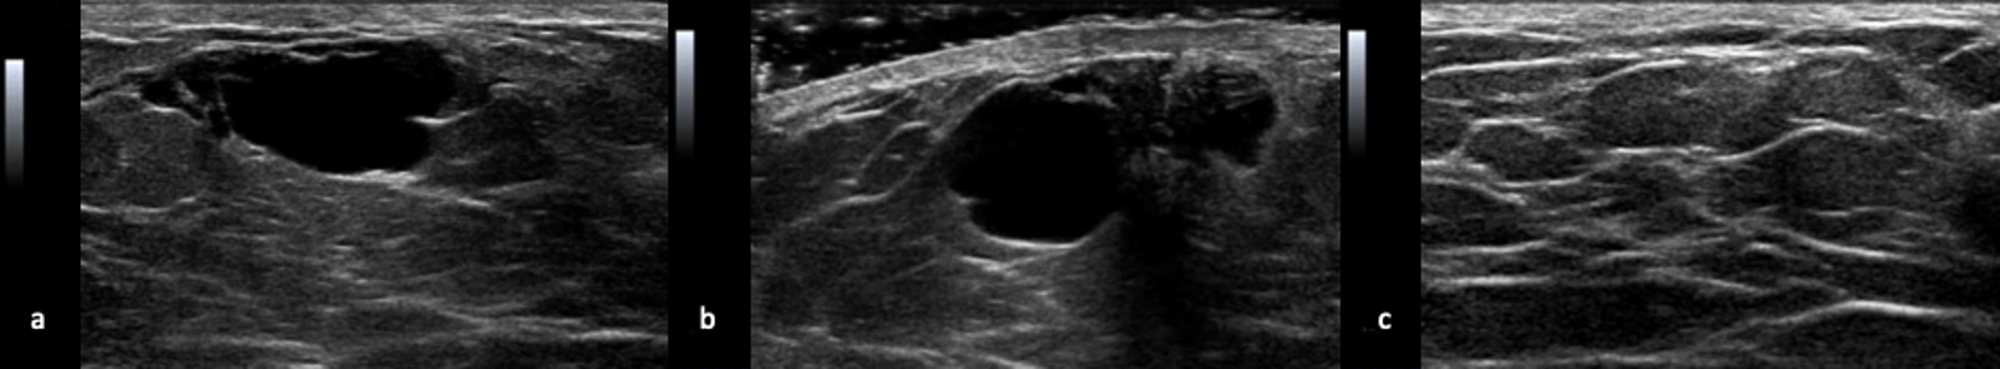

A left breast ultrasound examination demonstrated a simple cyst measuring 12 x 8 x 15 mm at the 12 o'clock position, corresponding to the palpable area with adjacent gynecomastia (Figure 2).

These imaging findings were consistent with a simple benign breast cyst and categorized as Low Suspicion for Malignancy (Bi-RADS (Breast Imaging-Reporting and Data System) category 4A) because, given the rarity of cysts in male patients, a biopsy was recommended for confirmation.

On mammography, cysts may be seen as solitary or multiple, unilateral or bilateral, low or equal density masses with round, oval, or occasionally lobulated borders. Their margins are usually well-circumscribed but may be partly obscured by breast parenchyma [3]. On ultrasound, cysts are typically seen as well-circumscribed anechoic masses with posterior acoustic enhancement [4].